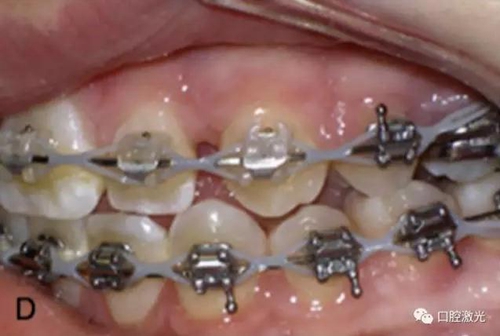

相比之下,激光開窗導(dǎo)萌有很多優(yōu)點,如果有足夠的角化組織,那么是可以采用激光進行開窗手術(shù)實施導(dǎo)萌,并立即粘接托槽。因此,同樣可以節(jié)省患者的等待時間。另外,口腔激光的止血特性可以提供清晰的視野,也有助于術(shù)后立即粘接托槽。

治療前

激光牙齦切割后即刻

粘接托槽

3周后效果